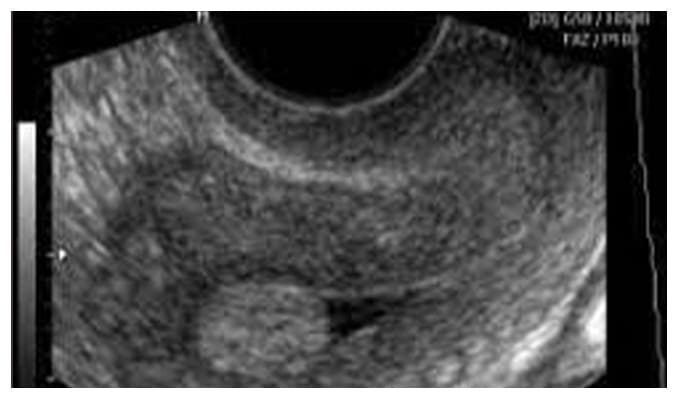

Síndrome de Ovario Poliquísticos